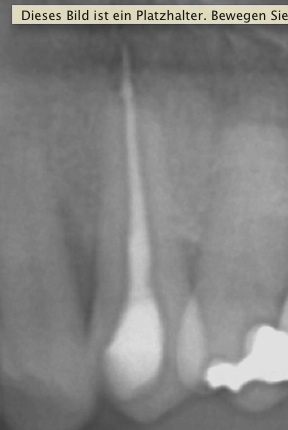

Ausgangssituation Veröffentlicht 6. Oktober 2010 am 288 × 430 in Thermafil – Revision (2) Ausgangssituation